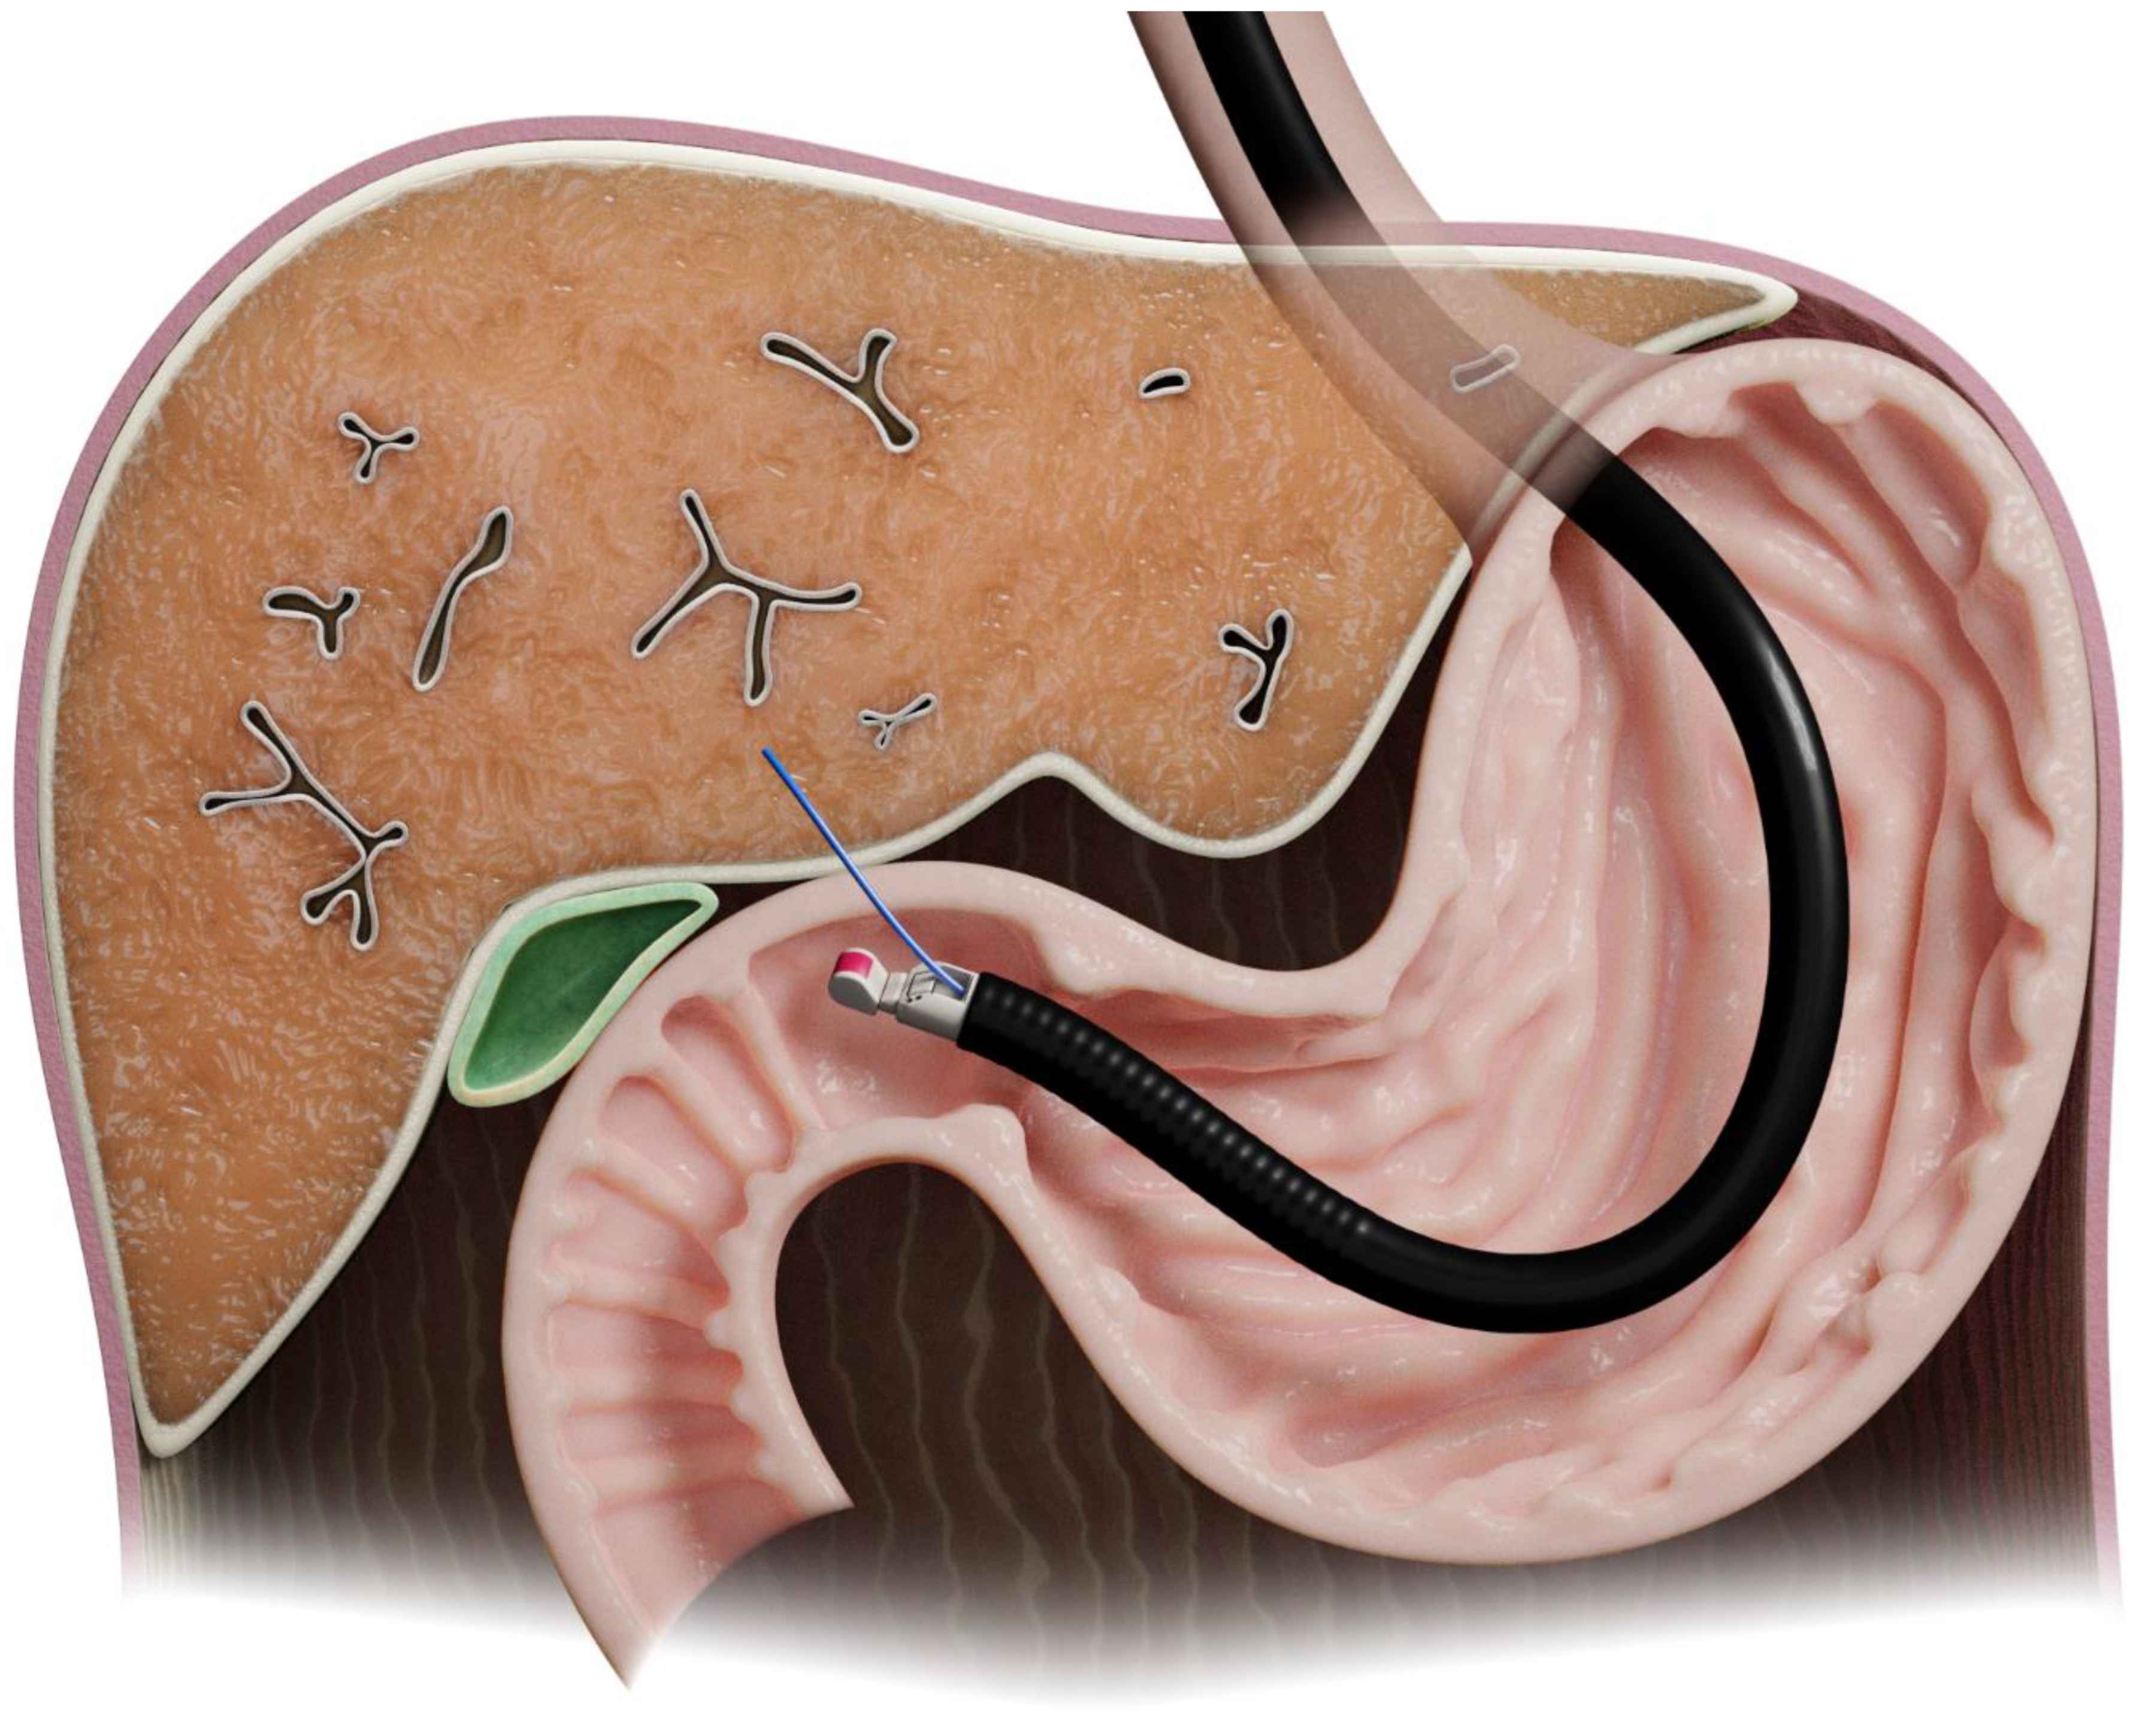

The first study of EUS-LB in humans was in 2006 [7]. The left lobe can be approached using ultrasound guidance from the proximal stomach, while the right lobe can be accessed from the duodenal bulb [8] (Figure 3).

Figure 3.

Illustration of endoscopic-ultrasound-guided liver biopsy.